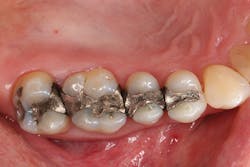

Figure 2: Hygienic nonlatex rubber-dam isolation was established; the existing amalgam restorations and decay were removed; and the preparations were refined, cleaned, and disinfected.